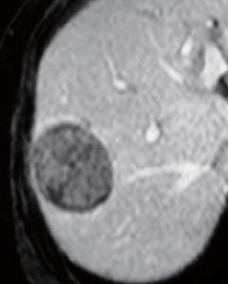

EOB-MRI findings

There was a high signal inside the tumor in in-phase, T1-weighted imaging; a low signal in opposed-phase, T1-weighted imaging; and a high signal in T2-weighted imaging (photographs not shown). Pre-contrast, fat-suppressed, T1-weighted imaging showed a low signal, and in the dynamic study the interior of the tumor showed a heterogeneous, low signal 20 s after administration, and slight contrast enhancement 60 and 120 s after administration, but the signal was lower than in the surrounding hepatic tissues. In the hepatobiliary phase, the tumor showed a low signal, but the surrounding tissue showed a small, low-signal, protrusion image, and the diagnosis made was simple-nodular HCC with extranodular proliferation.

Pre-contrast

20 s after administration

60 s after administration

120 s after administration

Hepatobiliary phase